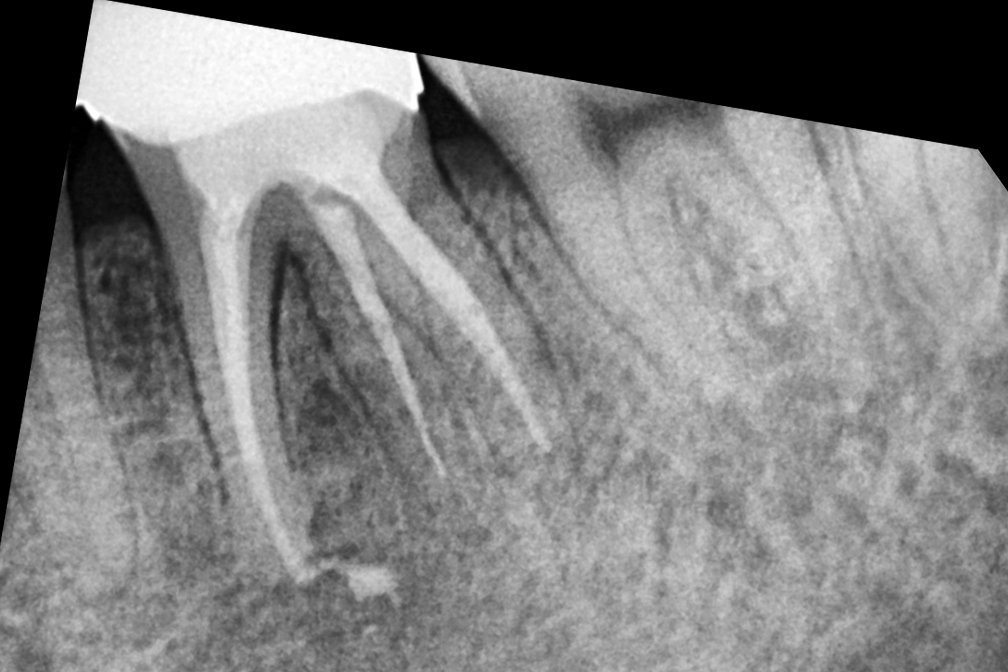

재신경치료

After 2026년 1월 24일